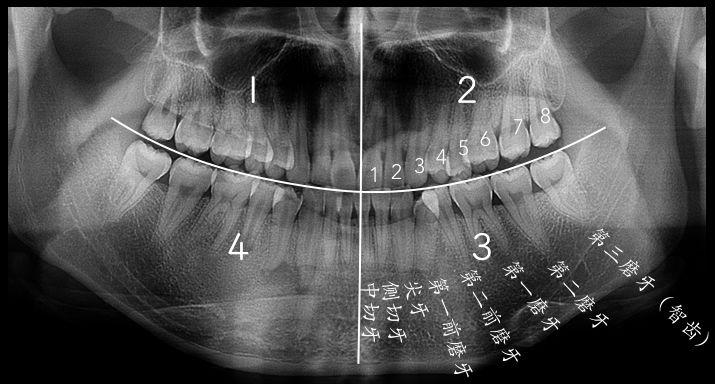

智齒的形態(tài)拔智齒的收費(fèi)依據(jù)價(jià)格的背后——牙醫(yī)知識(shí)的凝聚常見(jiàn)智齒的形態(tài)智齒是從正中的門(mén)牙往里數(shù)第八顆牙齒,也就是第三顆磨牙。它是發(fā)育、萌出晚的牙齒,通常在4~5歲時(shí)形成牙胚,隨后逐漸發(fā)育形成牙齒,一般17~25歲左右萌出,此時(shí)人的生理、心理發(fā)育都接近成熟,因此俗稱“智齒”。

智齒的形態(tài)也是各種各樣,簡(jiǎn)單可以羅列如下幾種,實(shí)際復(fù)雜遠(yuǎn)不止以下:

1、垂直高位

2、舌向高位

3、前傾高位

4、水平高位

5、垂直中位

6、舌向中位

7、前傾中位

8、水平中位

9、垂直低位

10、舌向低位

11、前傾低位

12、水平低位